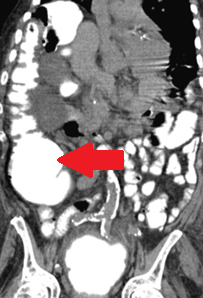

Η αξονική αγγειογραφία αποκάλυψε διάχυτες ασβεστώσεις του αγγειακού τοιχώματος και αθηροσκληρωτικές μεταβολές της κάτω κοιλιακής αορτής και των αμφοτερόπλευρων λαγόνιων αρτηριών, καθώς και έντονη ασβέστωση των μεγάλων και μικρών αρτηριών και των δύο κάτω άκρων. (Ευγενική παραχώρηση Dr. V. Penopoulos).